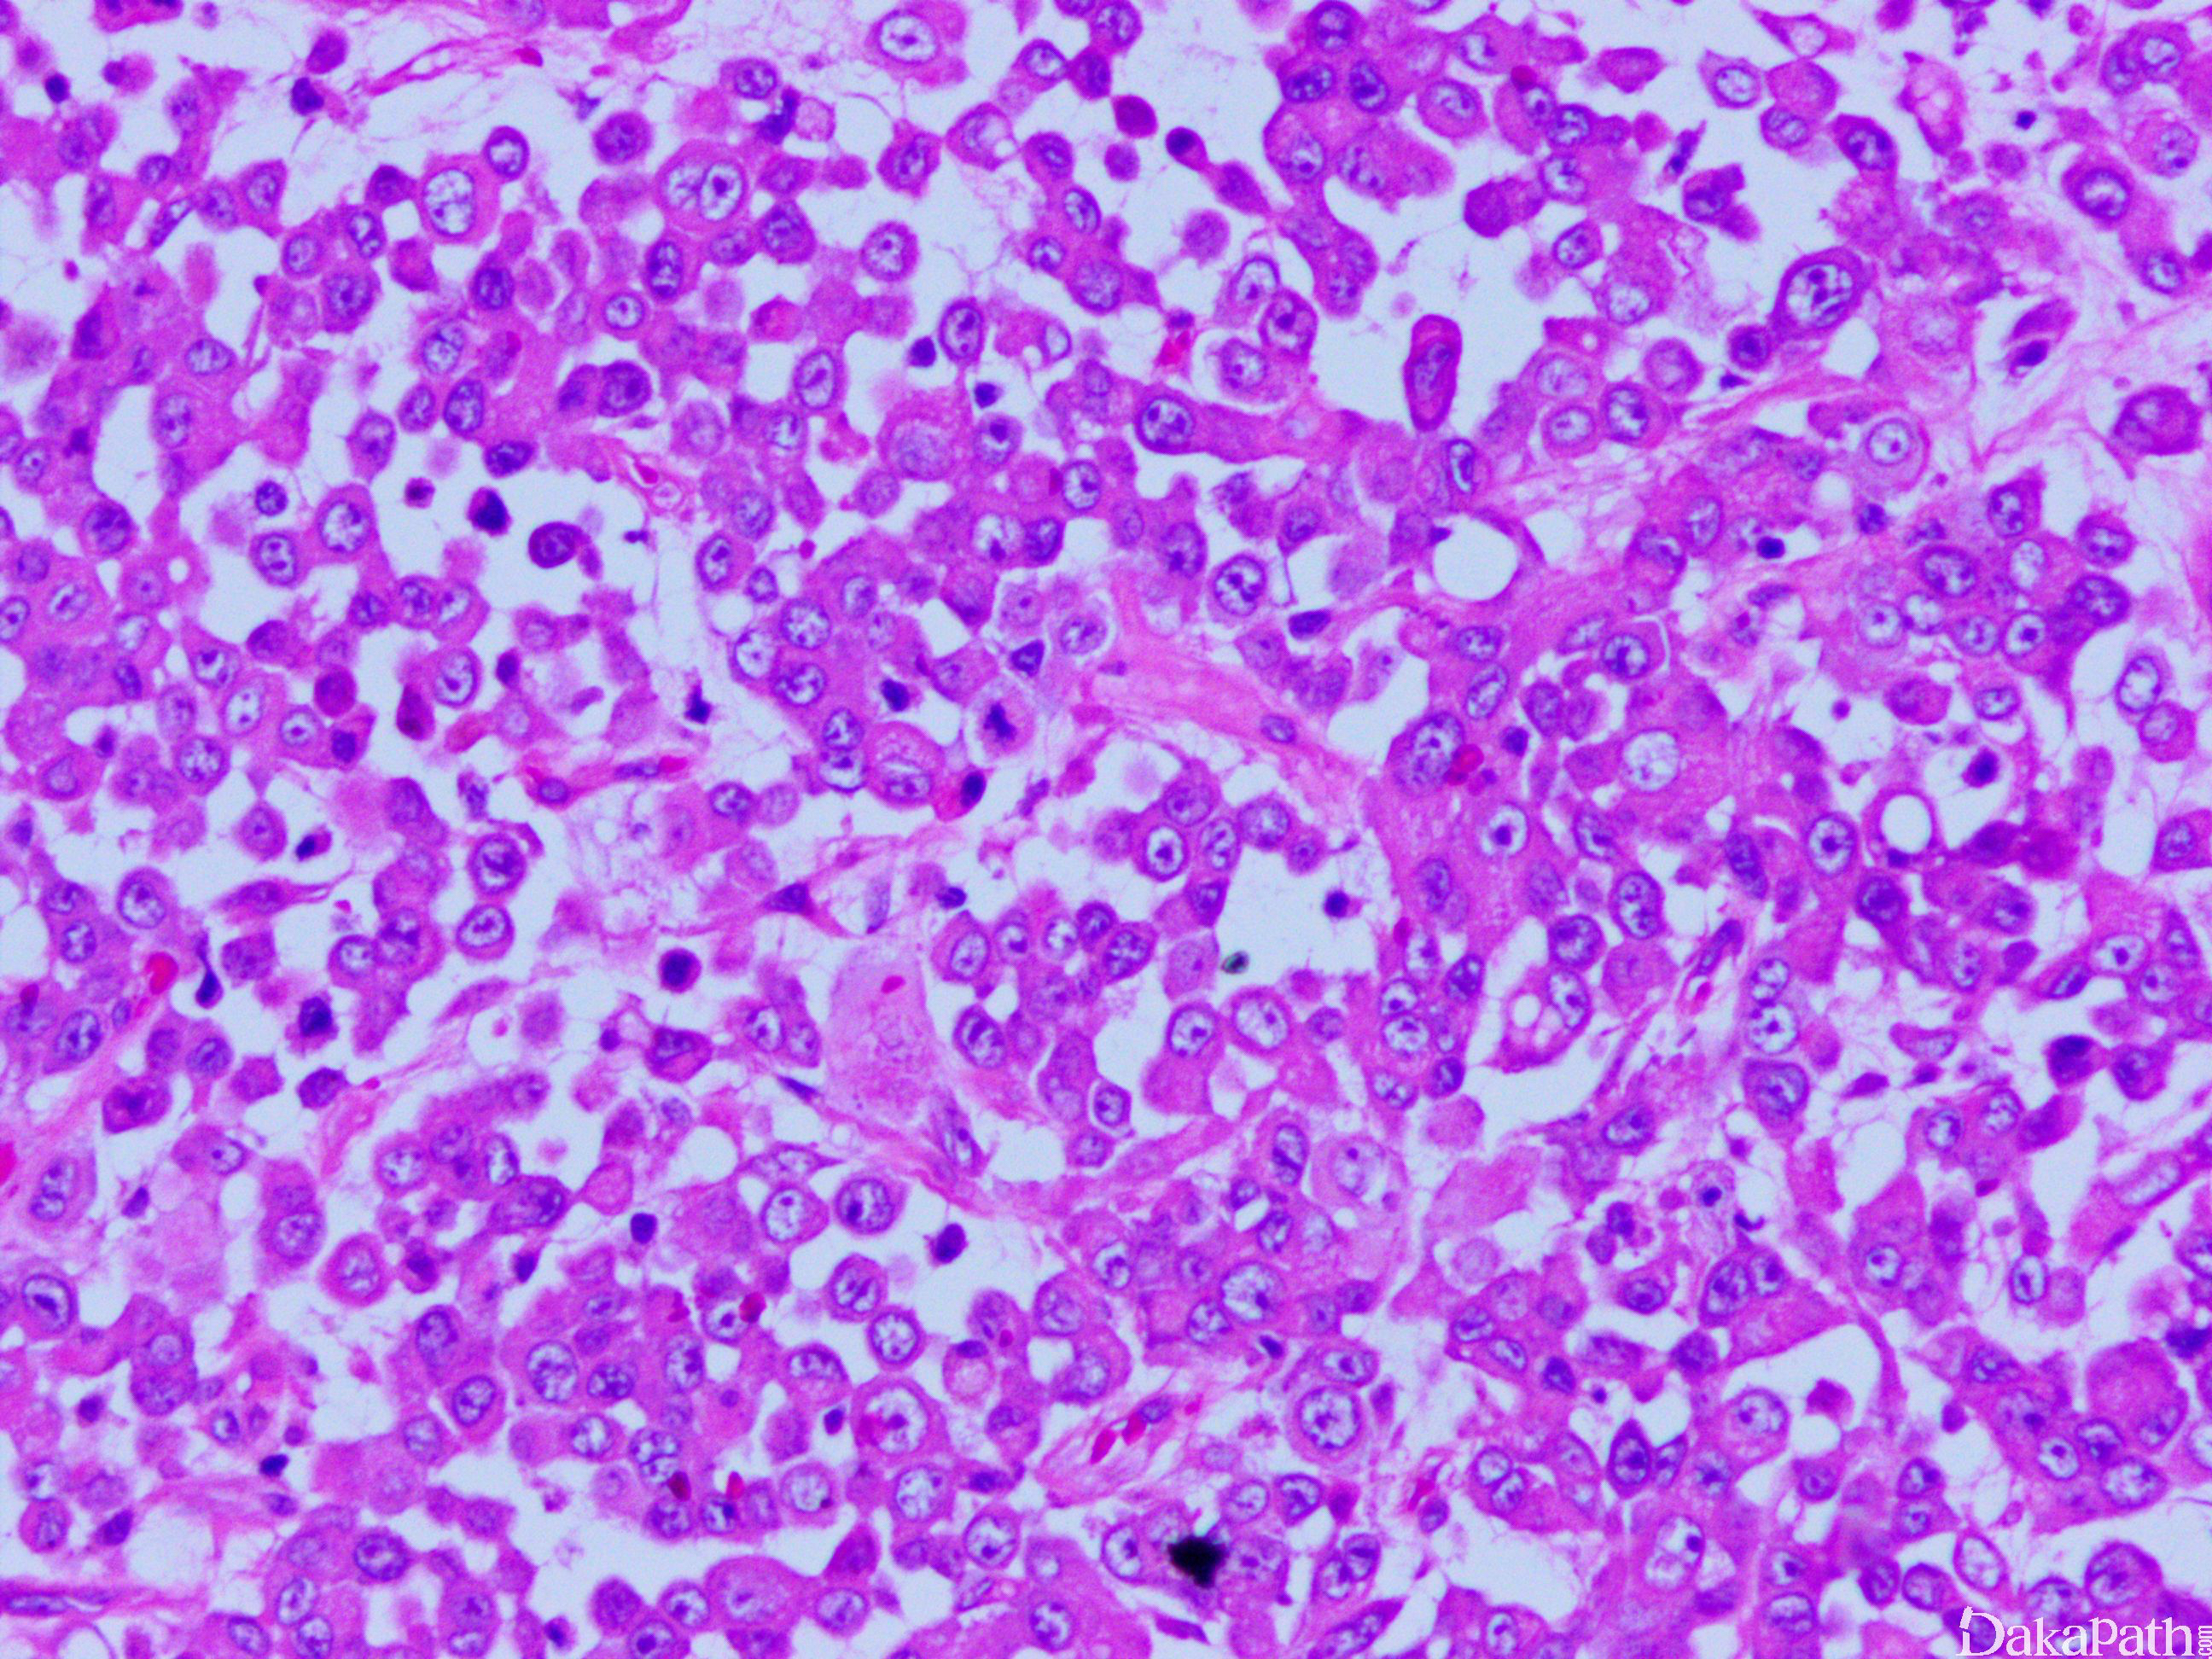

是发生于低龄儿童的具有高度侵袭性和致命性的肿瘤,肿瘤细胞有囊泡状染色质,核仁突出,细胞浆内有玻璃样变的包涵体。

- 镜下见成片的形态相对一致的恶性圆形细胞浸润至周围肾实质,常有广泛血管浸润;

- 肿瘤细胞有三个特点:囊泡状染色质,显著的红核仁和粉染玻璃样浆内包涵体,这些细胞在不同病例及同一病例不同视野多少不等;

- 部分病例可能主要由原始未分化小圆形细胞构成,但是仔细寻找可见灶状分布的诊断性横纹肌样细胞。